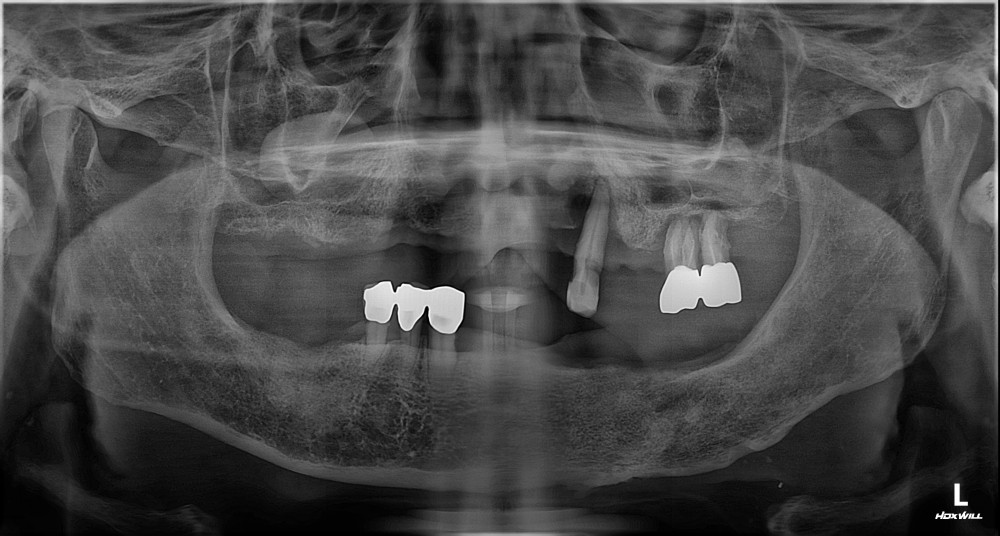

76세 / 남

방사선 전후 사진

위 임상사진은 광진정플란트치과의원에서 진료를 시작하고 마친 동일한 환자의 사진입니다.

위 임상사진은 동일조건으로 촬영되었으며, 사진에 대한 별도의 조작이 처리되지 않았습니다.